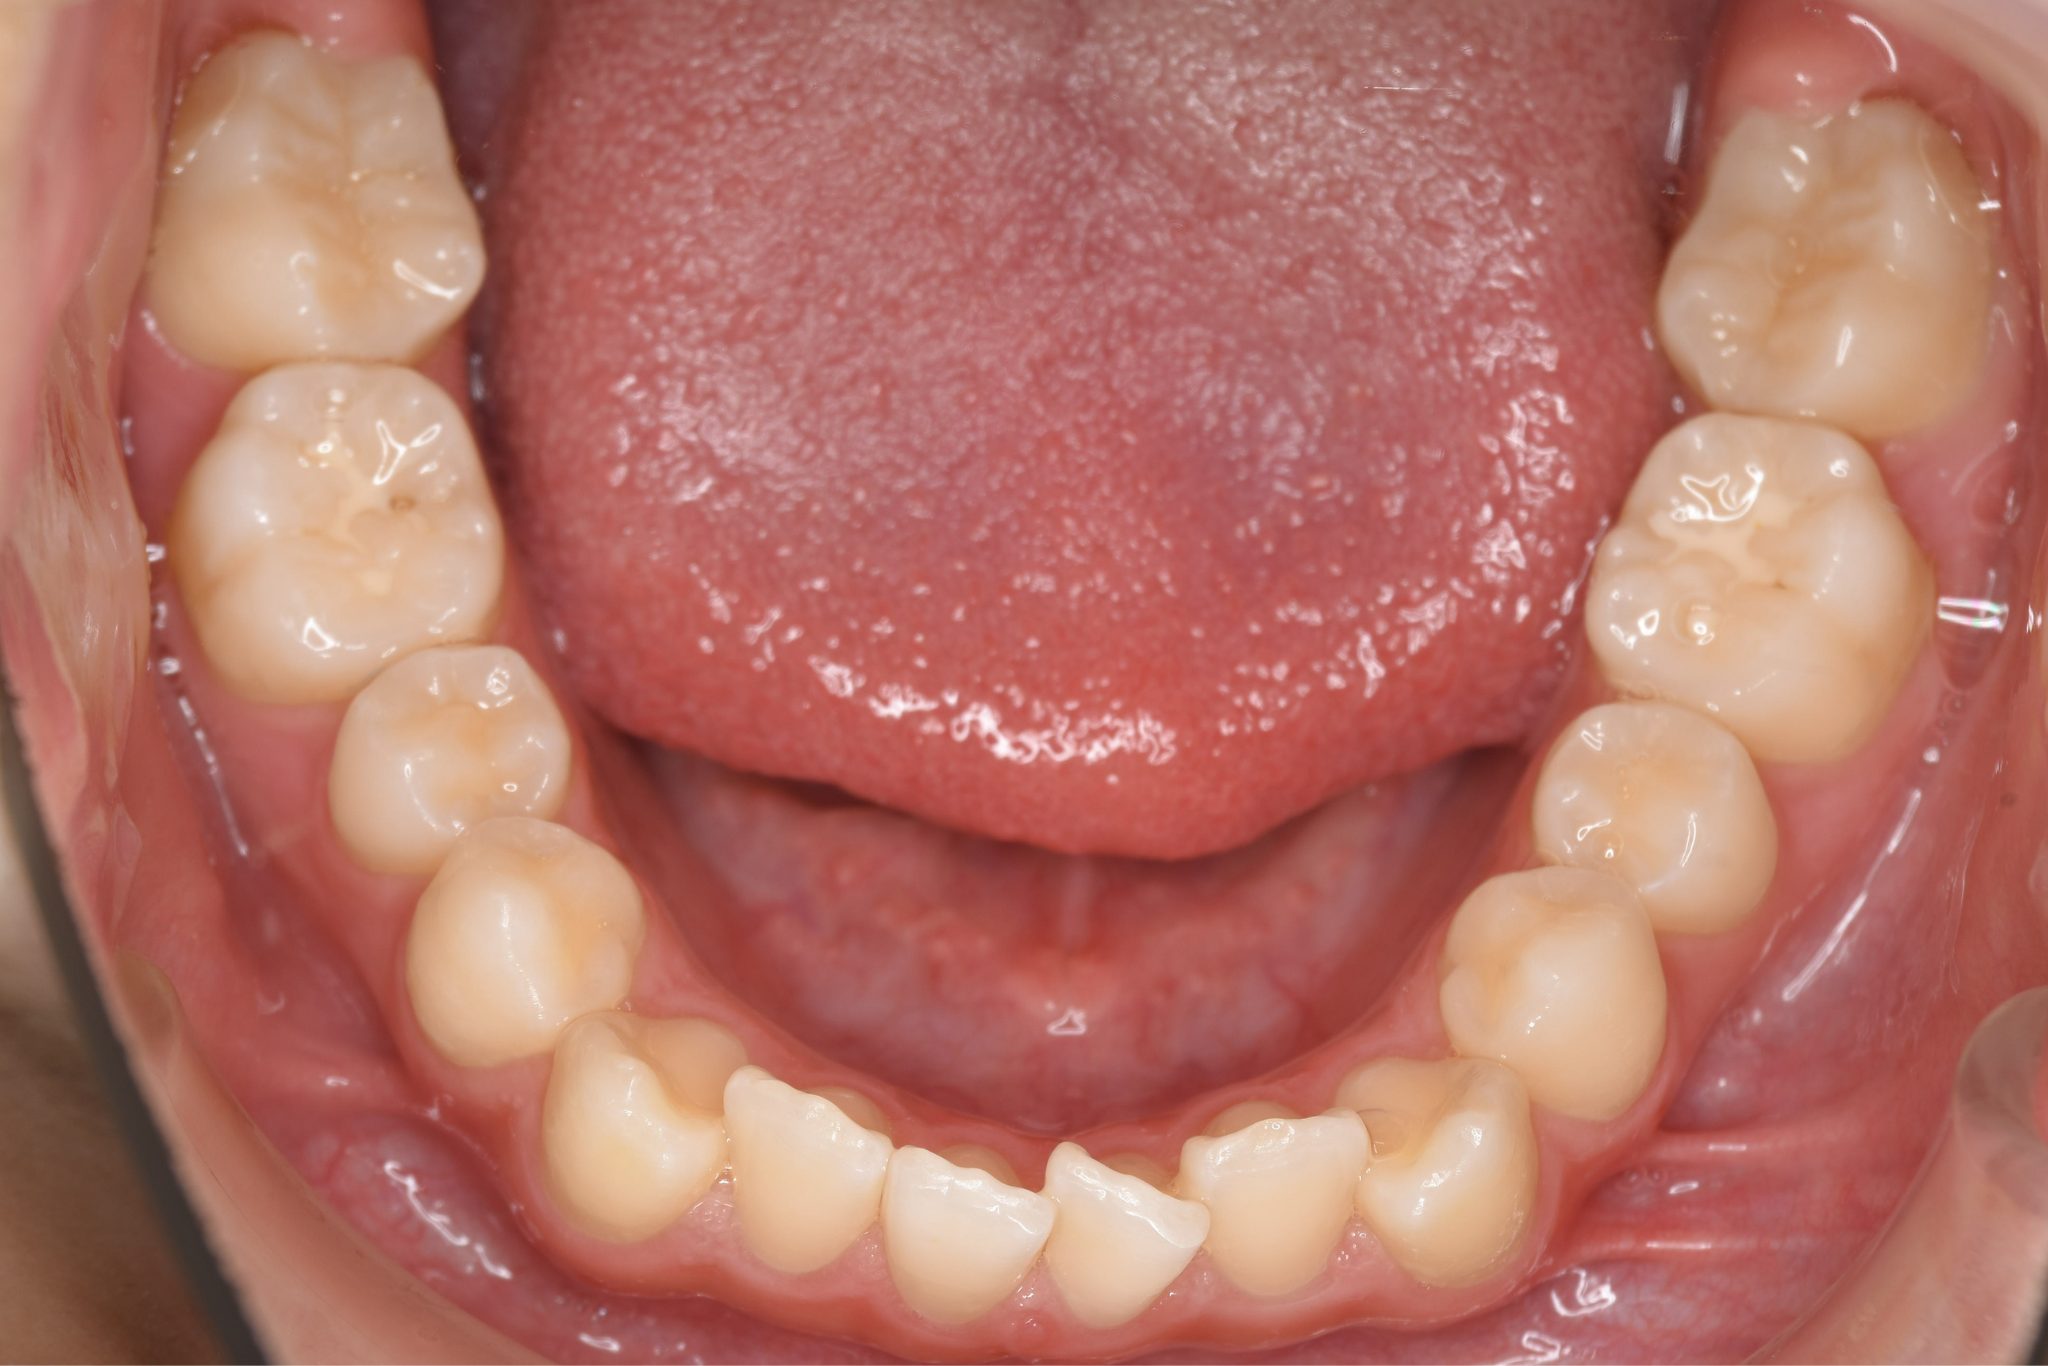

ビフォー

全顎ワイヤー矯正 症例_185

主訴 歯並び|横から生えている大人の歯

施術内容 小児矯正1期治療

治癒期間 4年間

費用 522,960円(税込)

リスク・副作用 違和感、不快感、痛み